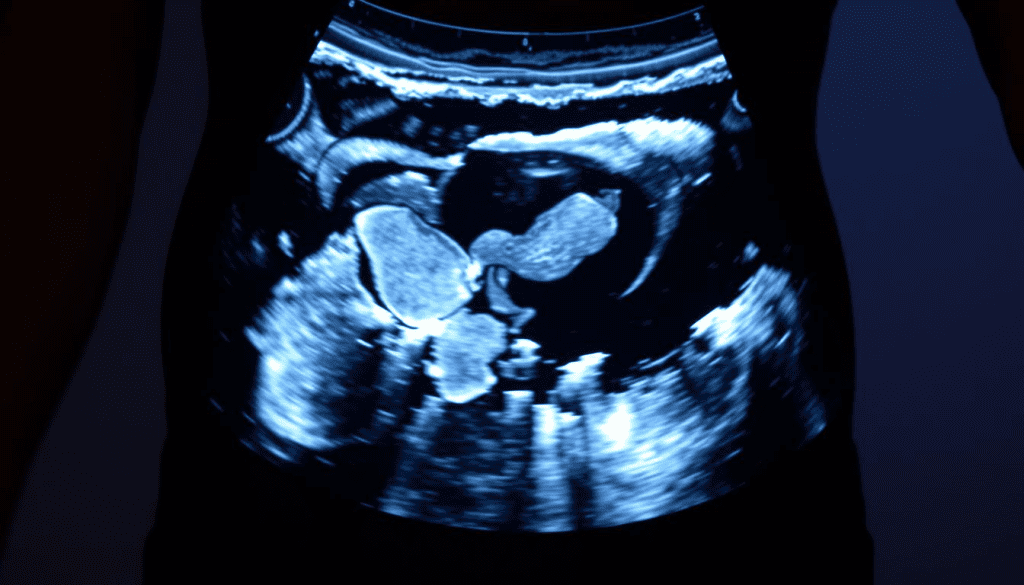

Pregnancy Ultrasound Considerations

Pregnancy ultrasounds are key in prenatal care. For transabdominal ultrasounds, a full bladder is needed. Drink water before to fill your bladder. Transvaginal ultrasounds require an empty bladder. We give specific instructions for each type.